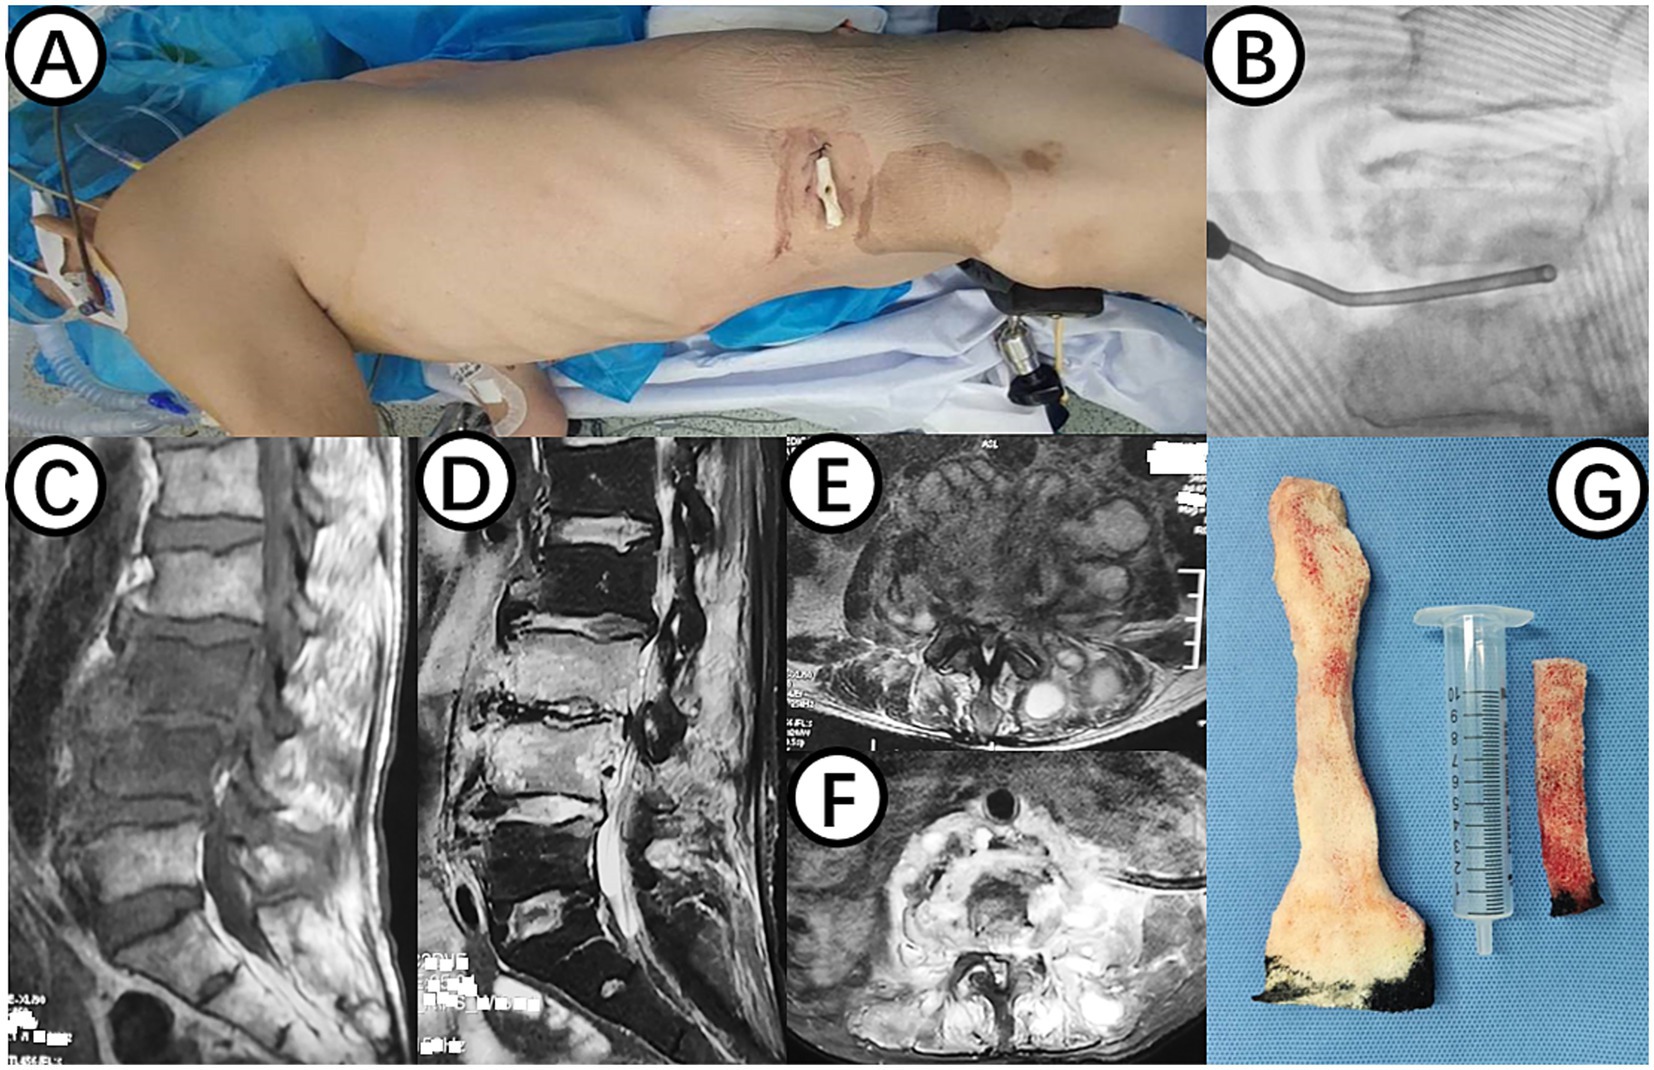

Figure 1

(A) Shows the surgical position for changing NPWT. (B) Displays intraoperative C-arm fluoroscopy positioning. (C,E) Present preoperative MRI scans showing high signal in the L3 and L4 vertebral bodies and intervertebral space, as well as abscess in the intervertebral space, bilateral lumbar muscles, and paraspinal muscles. (D,F) Demonstrate postoperative MRI showing decreased inflammation and edema signals in the L3 and L4 vertebral bodies and intervertebral space, with negative pressure sponge and drainage tube in place. (G) Depicts the NPWT sponge inside the body being replaced.

On July 20, 2023, a procedure was performed to clear the lesion in the lumbar spine using an extreme lateral approach. The abdominal external oblique muscle, internal oblique muscle, and transverse abdominal muscle were bluntly dissected to expose the peritoneum perioperatively. The lumbar erector spinae muscle was then exposed, showing swelling and severe inflammation. A purulent abscess was found within the lumbar erector spinae muscle, which was thoroughly drained. The L3/4 vertebral body and intervertebral space were exposed, and necrotic and purulent tissues were completely removed. The wound was thoroughly cleaned, with a small amount of fresh blood oozing from the intervertebral space. A NPWT sponge was placed in the L3/4 intervertebral space (Figures 1A,B), covered with a biological dressing and continuous negative pressure suction, with no obvious air leakage observed.

On July 28, 2023, the patient underwent the second minimally invasive lateral approach lumbar spine lesion clearance surgery. Approximately 355 mL of fluid was drained postoperatively for 7 days. Prior to the surgery, a follow-up MRI was performed, which showed significant improvement at the site of the lesion (Figures 1D,F). On August 4, 2023, the patient underwent the third minimally invasive lateral approach lumbar spine lesion clearance surgery. During the surgery, necrotic tissue was scraped from the intervertebral space, the wound was thoroughly cleaned, and a NPWT negative pressure drainage was replaced (Figure 1G). On the third day after surgery, the patient’s blood pressure was 80/55 mmHg, and blood tests showed a hemoglobin level of 52 g/L, an activated partial thromboplastin time (Activated Partial Thromboplastin Time) of 39.3 s, and a Thrombin Time (TT) of 22.2 s (The changes in coagulation indicators are detailed in Figure 2). The drainage volume reached 500 mL of bloody fluid in 24 h, indicating hypovolemic shock. Emergency exploration on August 7, 2023, revealed arterial blood oozing from the L3/4 intervertebral space with poor clotting. The coagulation parameters on the same day suggested that the patient was in a peak state of hypocoagulability (see Figure 2). The wound was irrigated with saline, electrocoagulated to stop the bleeding, and packed with gelatin sponge and hemostatic gauze. The wound was satisfactorily closed with a negative pressure drainage tube left in place. The patient received 4 units of red blood cells on the day of surgery. On the first postoperative day, the patient’s albumin level was 27.2 g/L, and hemoglobin level was 48 g/L. The patient received concentrated red blood cells (AB type), fresh frozen plasma (AB type), and cryoprecipitate, as well as furosemide injection and a saline solution with dexamethasone. The patient received 4 units of red blood cells, 600 mL of fresh frozen plasma, and 10 units of cryoprecipitate on the first postoperative day. On the second postoperative day, the hemoglobin level was 60 g/L, and the patient received 2 units of red blood cells, 610 mL of fresh frozen plasma, and 10 units of cryoprecipitate. On the third postoperative day, the blood pressure was 126/87 mmHg, the hemoglobin level was 87 g/L, and the albumin level was 37.7 g/L. The patient was given two units of red blood cells, resulting in a significant improvement in their anemia symptoms. Refer to Figure 3 for a detailed treatment process. MRI review indicates the presence of a hematoma in the surgical area (Figures 4A–C). After four effective debridement surgeries and antibiotic treatment, the lumbar spine infection improved gradually, and the retroperitoneal hematoma was absorbed. Follow-up abdominal MRI scan after 3 months showed an encapsulated fluid signal in the retroperitoneum (Figures 4D–F).